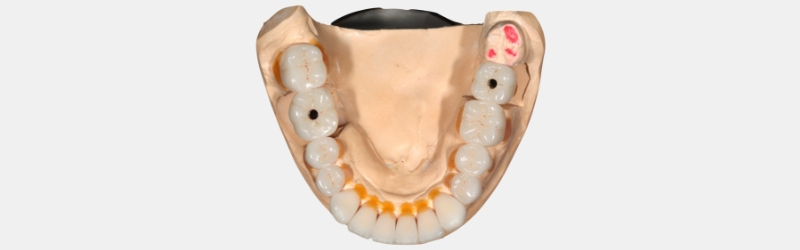

Visual Essay: Implant Crown Restorative Challenges and Solutions